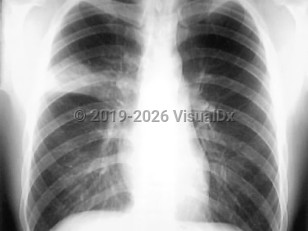

Community-acquired pneumonia